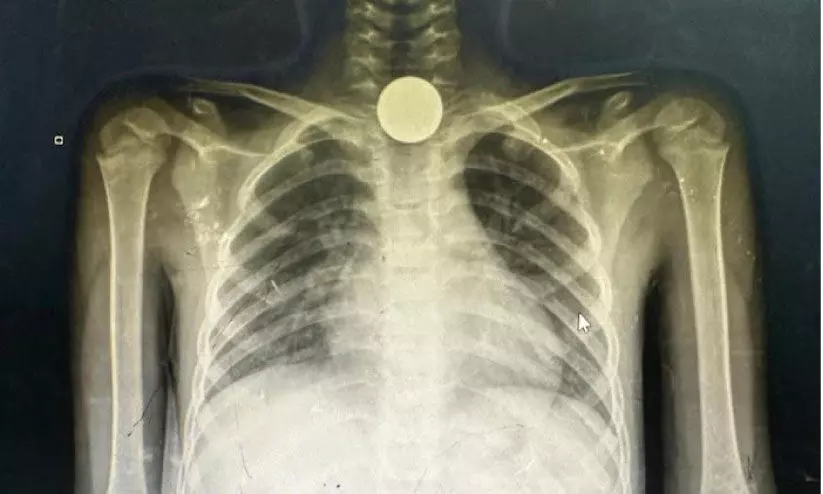

text_fieldsഡോ. ഖാലിദ് അൽ ശമൂസി എക്സിൽ പങ്കുവെച്ച എക്സ് റേ ചിത്രം

എഫ്.എ.ജെ.ആർ ശാസ്ത്ര സംഘടനയുടെ സഹായത്തോടെ വിവിധ സ്പെഷാലിറ്റികളിൽനിന്നുള്ള ഡോക്ടർമാരുടെ സംഘത്തോടൊപ്പം മേയ് രണ്ടിനാണ് ശമൂസി ഗസ്സയിലെത്തിയത്. ഗസ്സയിലെ കുരുന്നുകൾ വിശപ്പടക്കാനായി നാണയങ്ങളും ഉരുളൻ കല്ലുകളും ചെറിയ ബാറ്ററികളും കഴിക്കുന്നുണ്ടെന്ന് എട്ട് വയസ്സുകാരന്റെ അന്നനാളത്തിൽ കുടുങ്ങിയ ലോഹക്കഷണത്തിന്റ എക്സ് റേയുടെ ഫോട്ടോ പങ്കിട്ട് ഡോക്ടർ പറഞ്ഞു. മറ്റൊരു അഞ്ചുവയസ്സുകാരിയുടെ ശരീരത്തിൽനിന്നും വാച്ചിന്റെ ബാറ്ററിയാണ് വേർതിരിച്ചെടുത്തത്. ഇത്തരത്തിലുള്ള ചികിത്സക്കായി ഗസ്സയിൽ എൻഡോസ്കോപ്പിസ്റ്റ് ഇല്ല. പെൺകുട്ടിയോടുള്ള ദൈവത്തിന്റെ കാരുണ്യം കാരണം അന്ന് ഞാൻ ഗസ്സയിലായിരുന്നു. അതുകൊണ്ട് ആ കുട്ടിയെ രക്ഷിക്കാനായി.